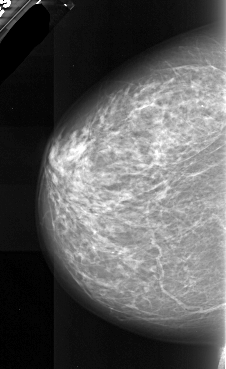

ics_version 1.0 filename A-1087-1 DATE_OF_STUDY 23 12 1997 PATIENT_AGE 61 FILM FILM_TYPE REGULAR DENSITY 3 DATE_DIGITIZED 12 2 1998 DIGITIZER DBA 21 SEQUENCE LEFT_CC LINES 5896 PIXELS_PER_LINE 3616 BITS_PER_PIXEL 16 RESOLUTION 42 NON_OVERLAY LEFT_MLO LINES 6691 PIXELS_PER_LINE 3706 BITS_PER_PIXEL 16 RESOLUTION 42 NON_OVERLAY RIGHT_CC LINES 5596 PIXELS_PER_LINE 3646 BITS_PER_PIXEL 16 RESOLUTION 42 OVERLAY RIGHT_MLO LINES 6931 PIXELS_PER_LINE 3811 BITS_PER_PIXEL 16 RESOLUTION 42 OVERLAY |

FILE: A_1087_1.RIGHT_MLO.OVERLAY TOTAL_ABNORMALITIES 1 ABNORMALITY 1 LESION_TYPE MASS SHAPE ARCHITECTURAL_DISTORTION MARGINS SPICULATED ASSESSMENT 5 SUBTLETY 1 PATHOLOGY MALIGNANT TOTAL_OUTLINES 2 BOUNDARY CORE |

FILE: A_1087_1.RIGHT_CC.OVERLAY TOTAL_ABNORMALITIES 1 ABNORMALITY 1 LESION_TYPE MASS SHAPE ARCHITECTURAL_DISTORTION MARGINS SPICULATED ASSESSMENT 5 SUBTLETY 1 PATHOLOGY MALIGNANT TOTAL_OUTLINES 2 BOUNDARY CORE |